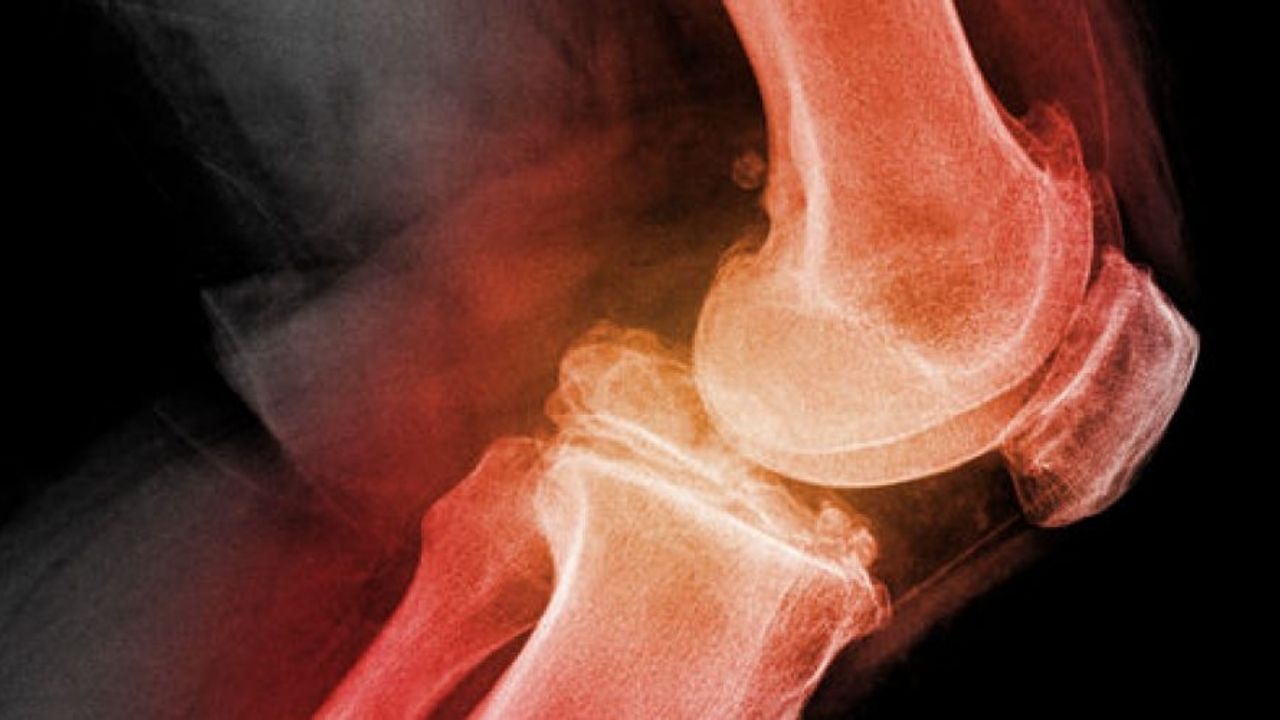

O ortopedista geral cuida de dores nas articulações, músculos, ossos e coluna, além de problemas como artrose, tendinites, bursites, lombalgia, entre outros.